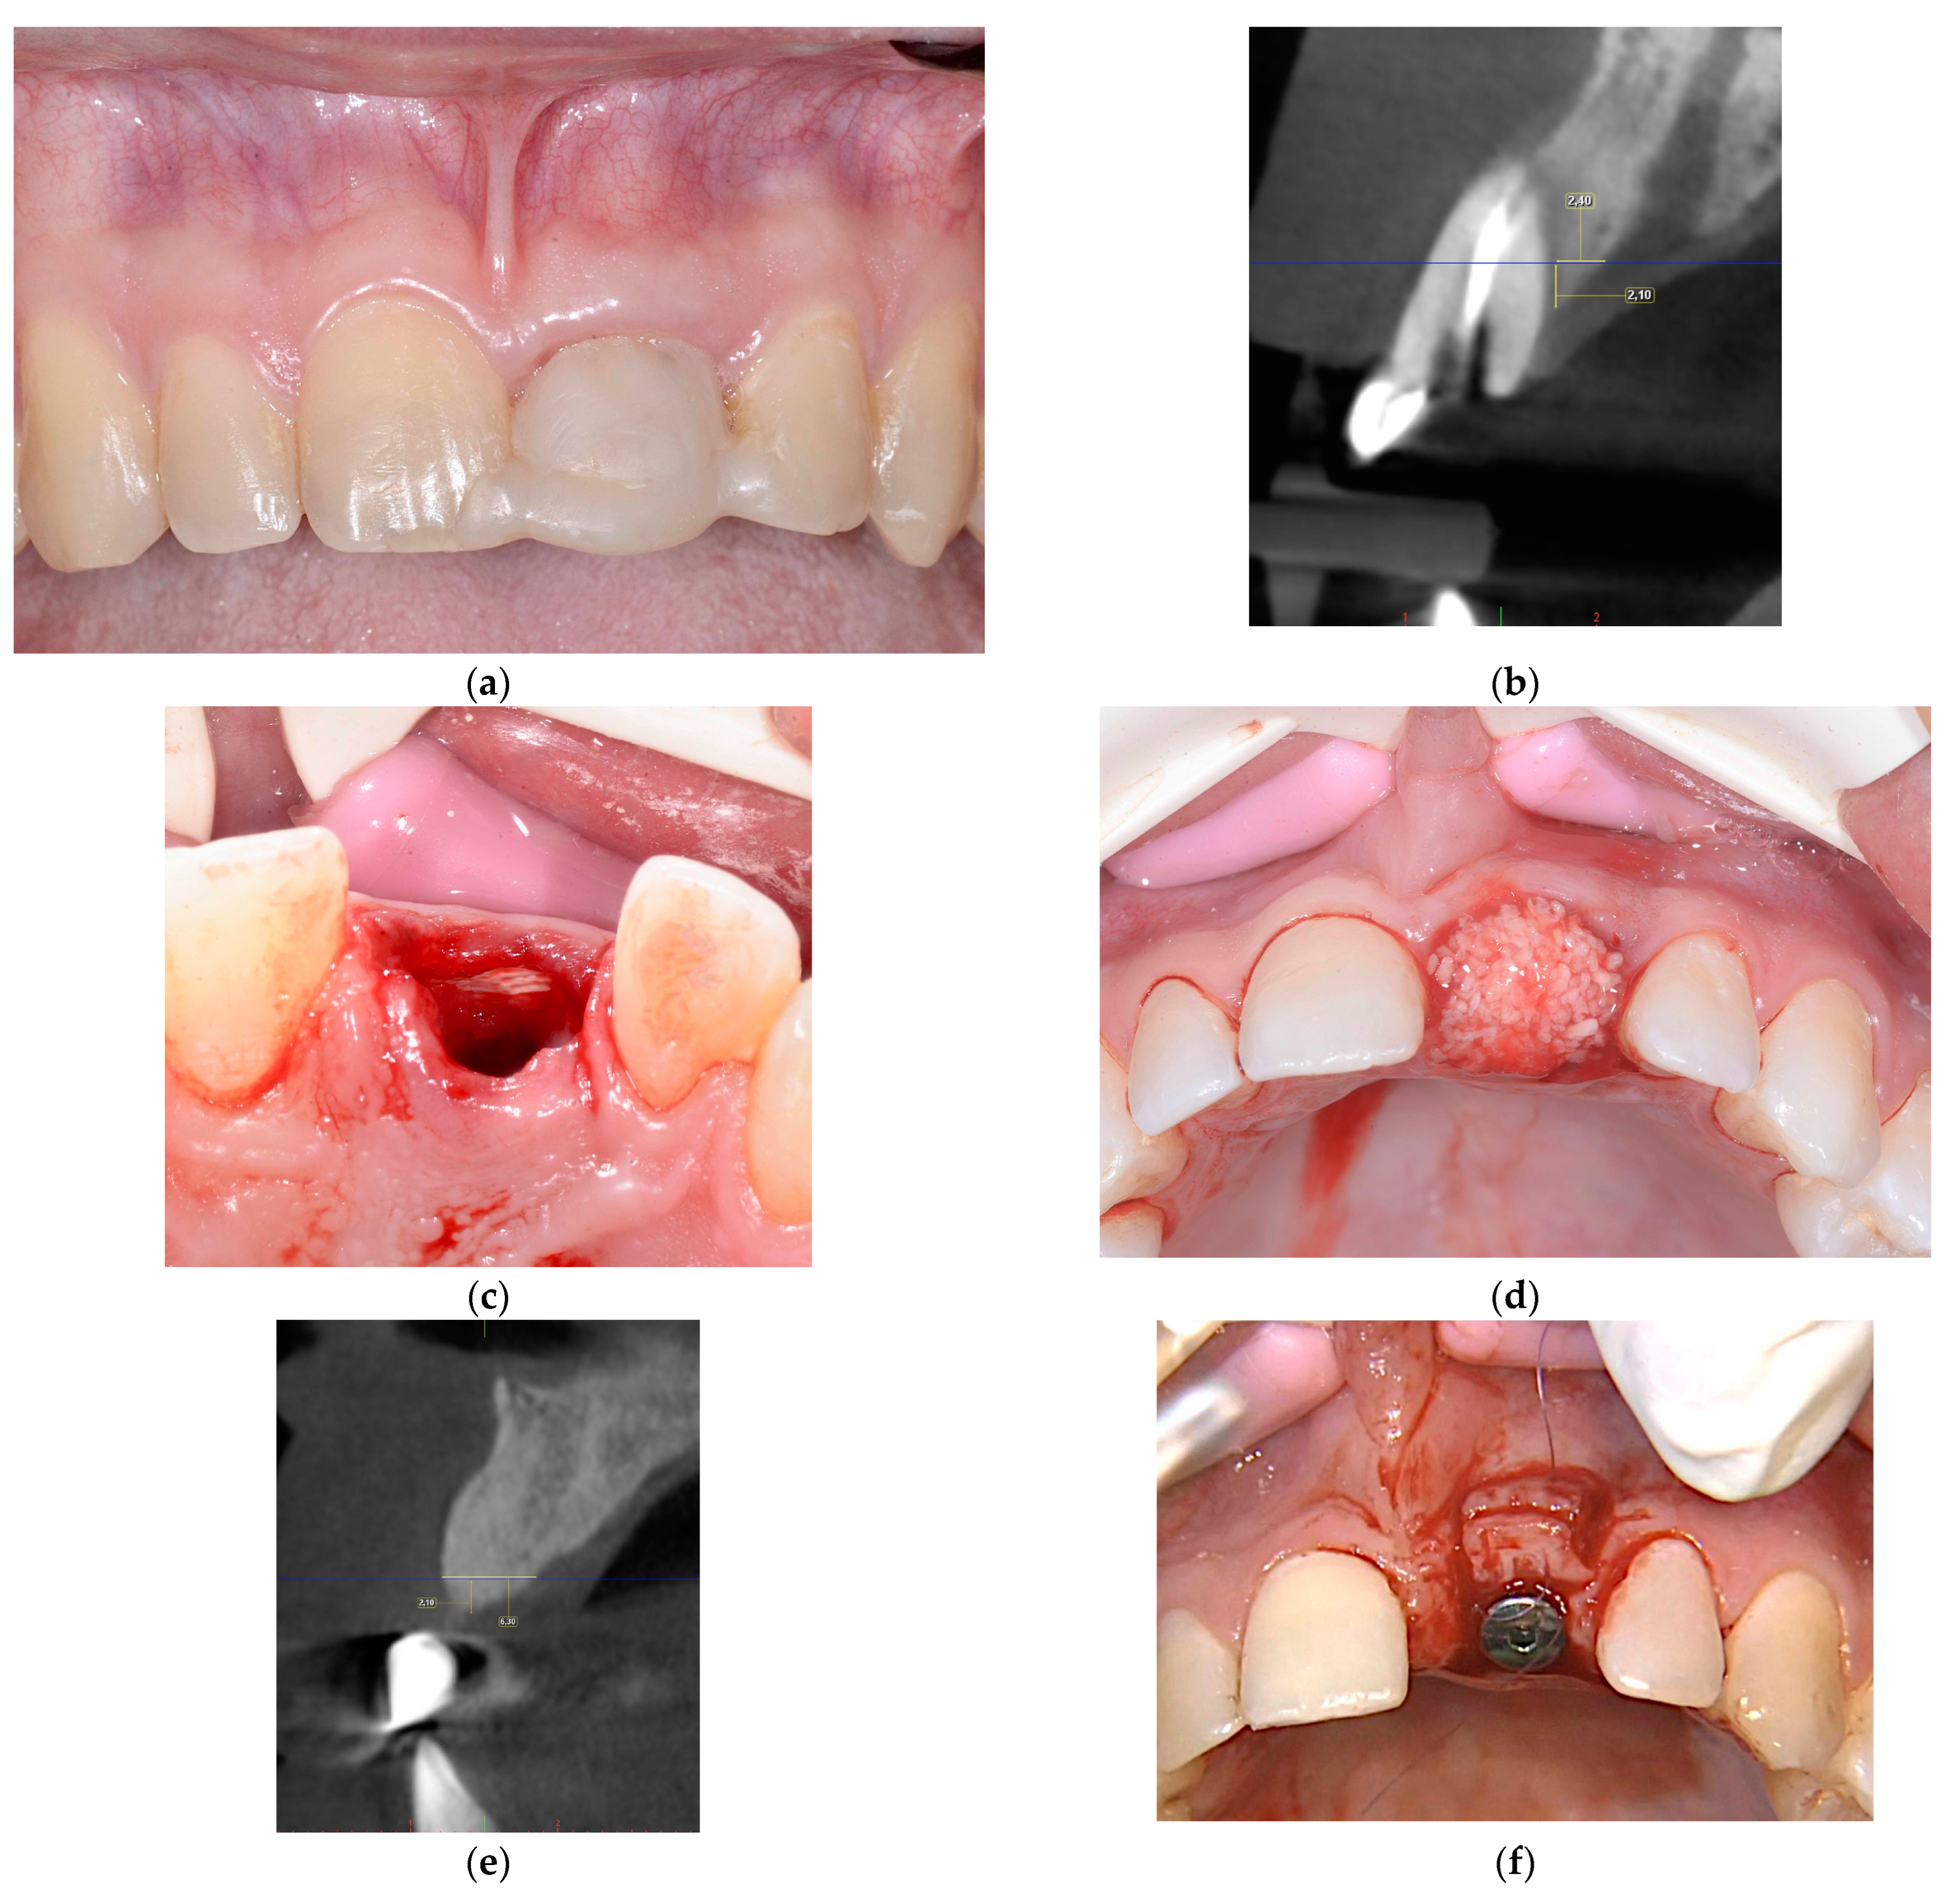

2.2.3. ARP and Delayed Implant Placement Using F.I.R.S.T.

- Foti, V.; Rossi, R. Fibrinogen-induced regeneration sealing technique (first) an improvement and modification of traditional gbr: A report of two cases. Mod. Res. Dent. 2020, 5, 476–485. [Google Scholar]

- Foti, V.; Savio, D.; Rossi, R. One-time cortical lamina: A new technique for horizontal ridge augmentation. A Case Ser. Br. J. Healthc. Med. Res. 2021, 8, 22–30. [Google Scholar] [CrossRef]

- Foti, V. Fibrinogen-induced regeneration sealing technique (f.I.R.S.T.). In Building Better Bone: A Comprehensive Guide to gbr Techniques; Rossi, R., Ed.; Quintessence Publishing: Batavia, IL, USA, 2024; pp. 210–227. [Google Scholar]

- Faro, L.L.; Strappa, E.M.; Carù, F.G.; Nanni, M.; Invernizzi, M.; Testori, T. Rigenerazione ossea guidata con tecnica first (fibrin-induced regeneration sealing technique). Case report con evidenze istologiche. Quintessenza Internazionale Riv. Di Odontoiatr. 2023, 37, 10–21. [Google Scholar]